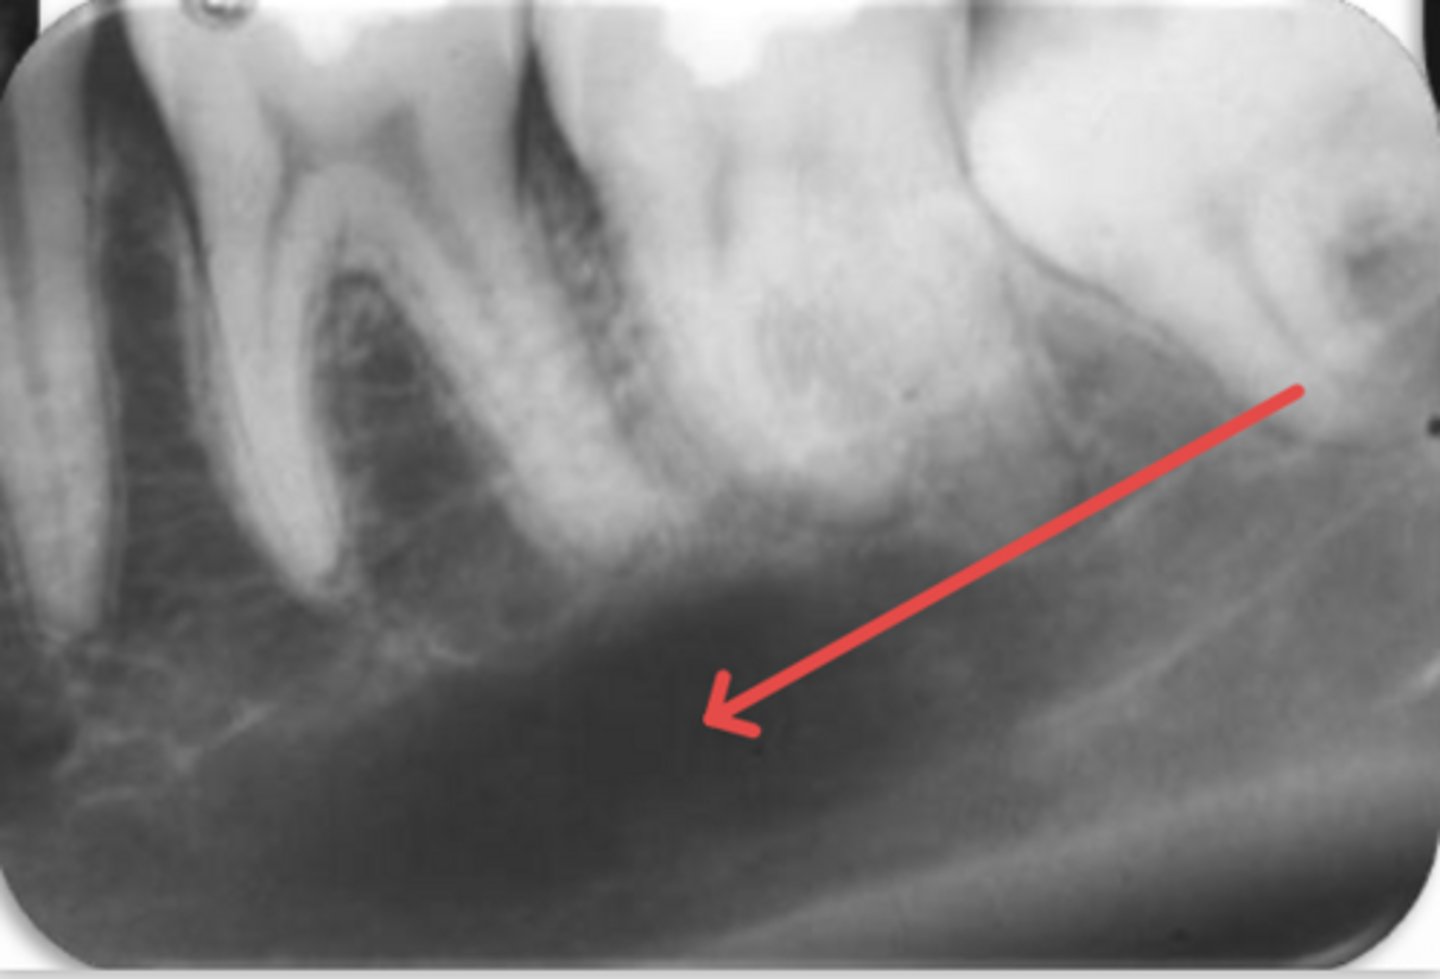

ID the problem:

external resorption